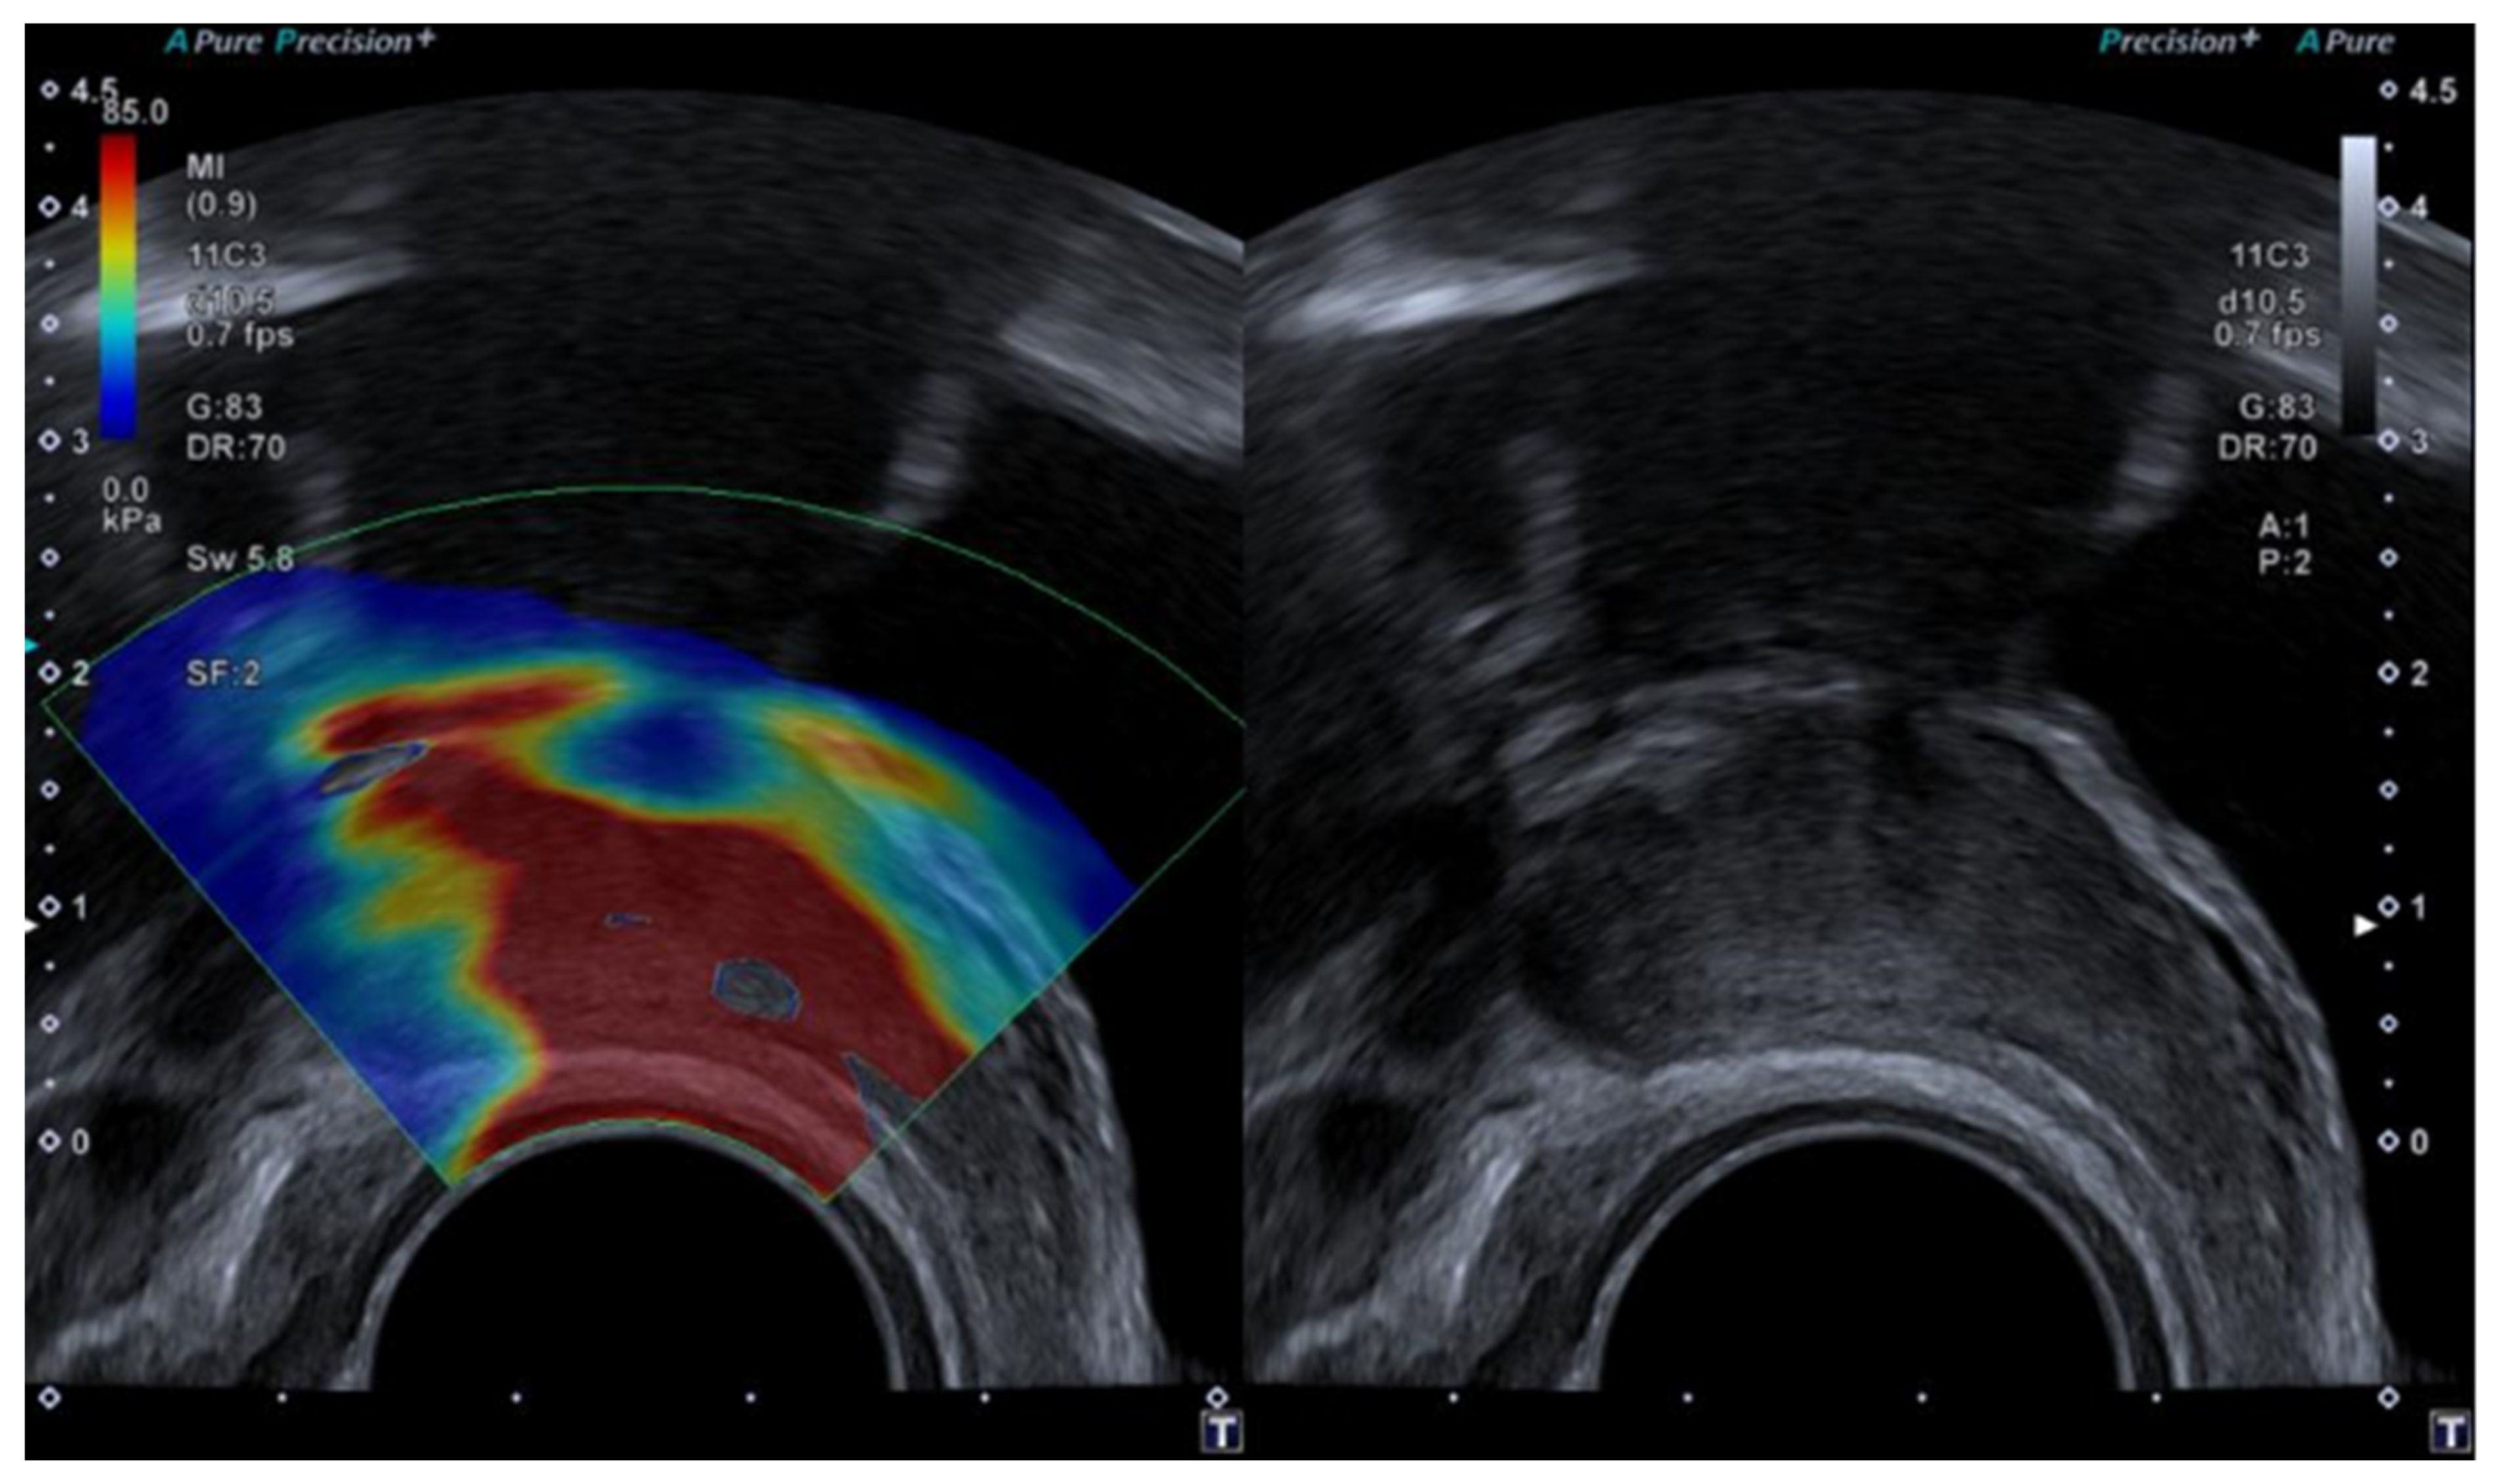

1.4.1. Strain or Compression Elastography

1.4.2. Shear Wave Elastography

3.3. Elastography in Prostate Lesions